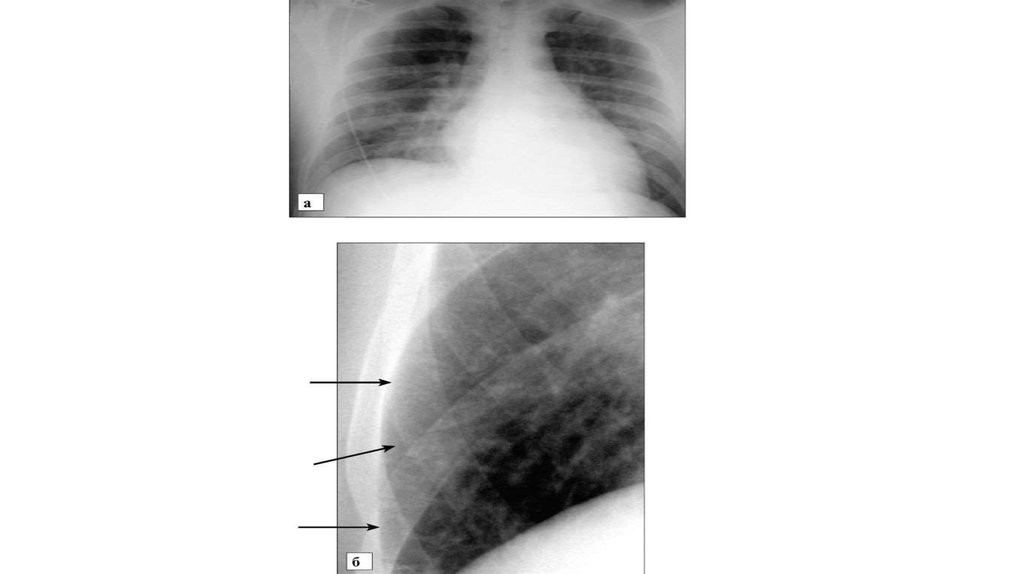

• Рентгенограмма в прямой проекции при интерстициальном отеке

легких:

а - определяется понижение прозрачности легочных полей,

малоструктурность корней, нечеткость контуров сосудов и бронхов;

б - видны линии Керли Б, идущие от плевры в медиальном

направлении (стрелки)